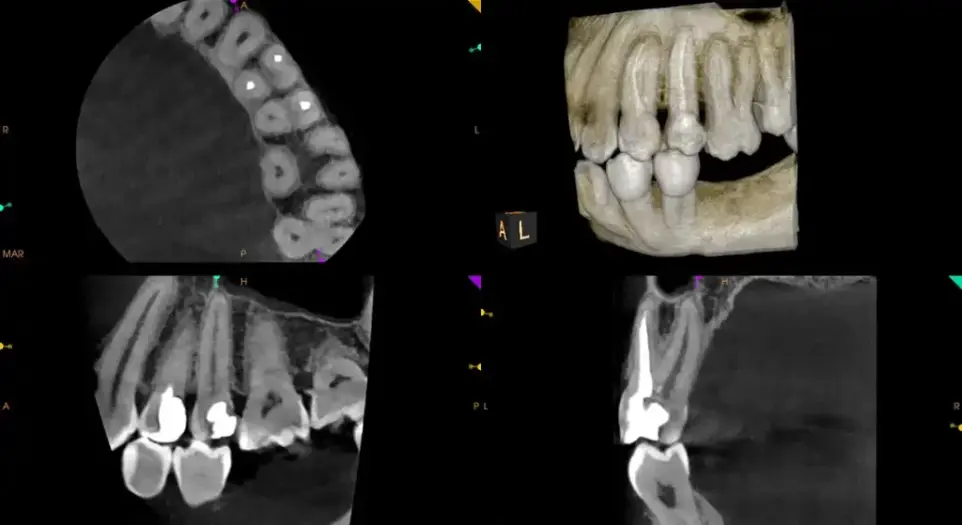

Discover the versatility of the CS 8200 3D, showing dynamic views of nerves, bone density, root structures, and airway pathways. This video demonstrates how its powerful 3D scans improve treatment accuracy even in the most complex cases.

Capture detailed 3D images of teeth, bone, nerves, and soft tissue—seeing what traditional X-rays often miss. Perfect for identifying complex issues early.

Each scan provides precise data for implants, root canals, TMJ therapy, or orthodontics, ensuring accuracy and comfort from day one.

Root Canal Therapy: Visualize every root and canal before treatment.